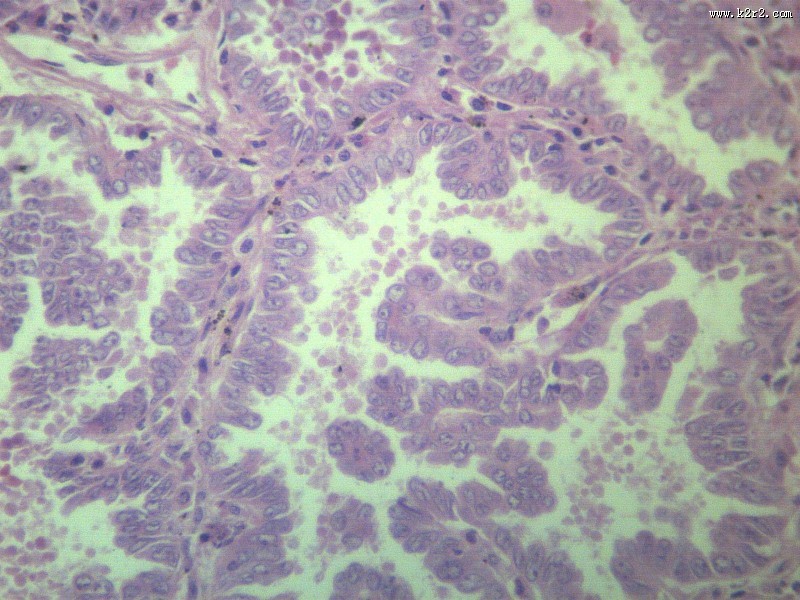

腺癌 - 第3张 共有

显微切片

肿瘤

腺癌

adenocarcinoma